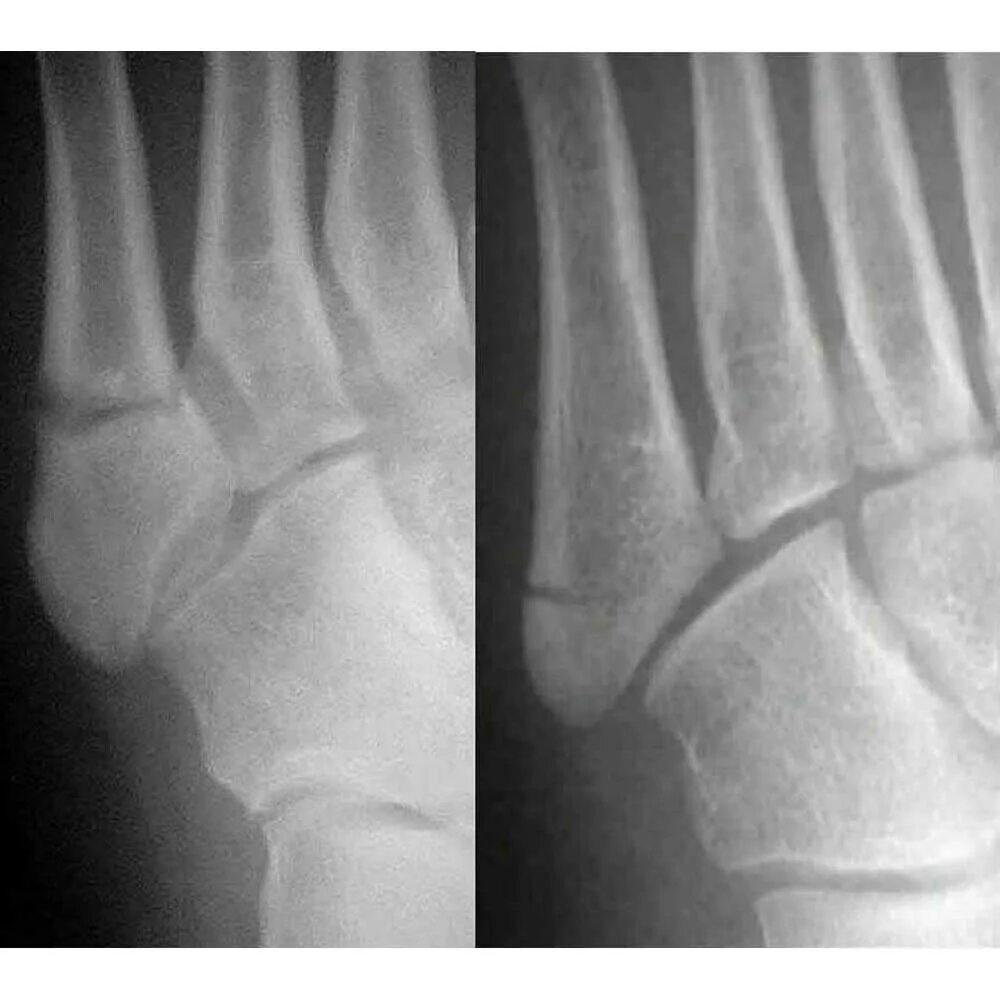

Сколько срастается стопа